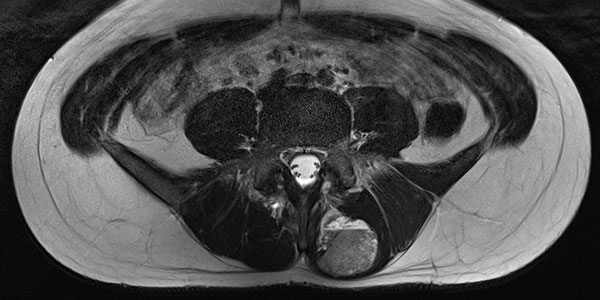

In der MRT in koronarer Schichtführung ist die Läsion sehr gut sichtbar. In der T2-gewichteten Sequenz mit Fettsättigung (linkes Bild) ist die Läsion stark hyperintens (weiß). In der nativen T1-Wichtung (rechtes Bild) praktisch isointens zur umgebenden Rückenmuskulatur. Beachte hier das randständig in der Läsion sichtbare, in T1-Wichtung hyperintense Fettgewebe.